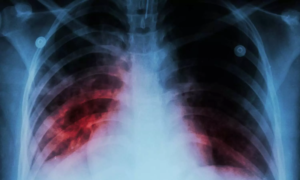

Pamrevlumab Shows No Significant Benefit in Slowing Lung Function Decline in Idiopathic Pulmonary Fibrosis: JAMA

Researchers have found that pamrevlumab, a monoclonal antibody,…